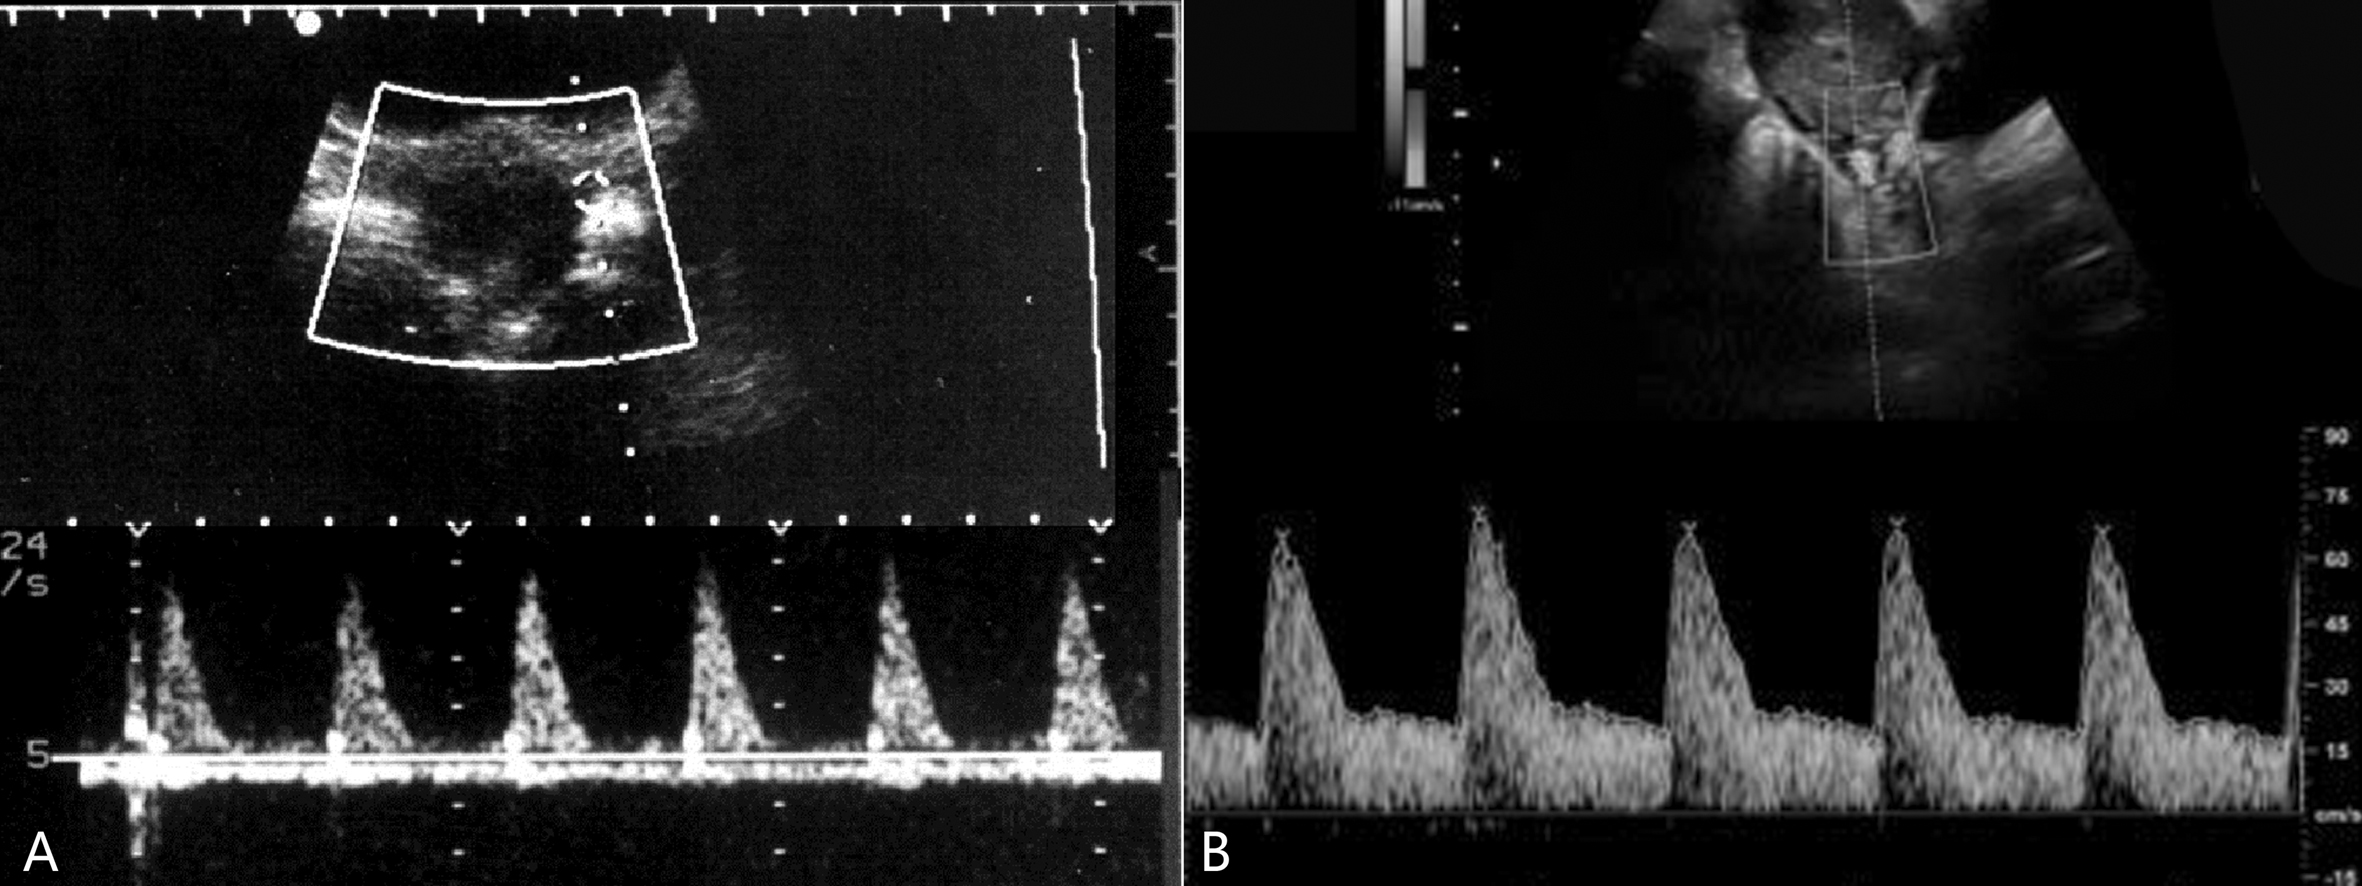

(三)子宫动脉血流速度曲线及正常参考值

尽管在月经不同时期子宫动脉血流有所不同,非孕期子宫动脉基本为高阻力血流频谱(图3A),国内一组研究资料统计了50例20~35岁健康非孕期妇女的子宫动脉血流,主要参考值:RI 0.79 ± 0.05,PI 2.08 ± 0.47,S/D 5.09 ± 1.26。从妊娠第6周开始子宫动脉血流即开始增加,并且主要表现为舒张期血流的增加,阻力下降,到第10周时下降就已经很明显(表1、图3B),随着妊娠的继续,子宫动脉的血流峰值速度逐渐增加,阻力指数和搏动指数逐渐降低(表1、图4C),至足月妊娠时形成典型的低阻力型血流(图4D)。

图3非孕期和妊娠期子宫动脉血流变化

A:非孕期子宫动脉显示高阻力血流速度曲线 B:11周妊娠子宫动脉显示舒张期血流速度增加

图4孕期子宫动脉血流变化

C:30周妊娠子宫动脉显示舒张期血流速度明显增加;箭头示子宫静脉持续、匀速的血流速度曲线;D:38周妊娠子宫动脉显示典型的低阻力型血流速度曲线